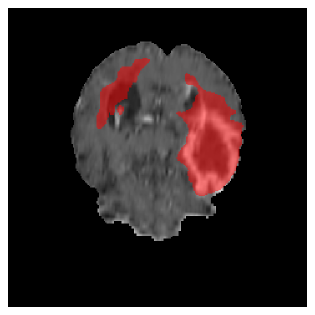

Appendix A Qualitative results

Figures 4 and 5 present the segmentation results for a patient from the BRATS dataset, visualized on a randomly selected slice. Figure 4 illustrates how tumor segmentation evolves over multiple episodes in S1 across different approaches including cumulative, naive, our approach, and the best buffer-free strategy (SI, =2). The cumulative approach, which trains on all encountered datasets together, maintains segmentation consistency across episodes but introduces significant amounts of false positives, particularly in the upper left area of the brain images. These misclassifications highlight its inability to generalize well across datasets despite access to all previous data. The naive approach, which learns sequentially without any continual learning strategy, suffers from severe catastrophic forgetting. While it initially segments well, performance deteriorates over episodes, leading to a near-complete loss of segmentation capability by the final episode. The SI (=2) approach, a regularization-based buffer-free CL strategy, performs reasonably well in early episodes but shows a significant performance decline over time. By the last episode, much of the tumor was no longer segmented, indicating difficulty in retaining prior knowledge. In contrast, our proposed approach initially produces more false positives but progressively refines its segmentation. By the final episode, it accurately retains the tumor region while minimizing misclassifications, demonstrating strong knowledge retention and adaptability across episodes. This suggests that our approach effectively mitigates catastrophic forgetting while maintaining segmentation performance over sequential learning.